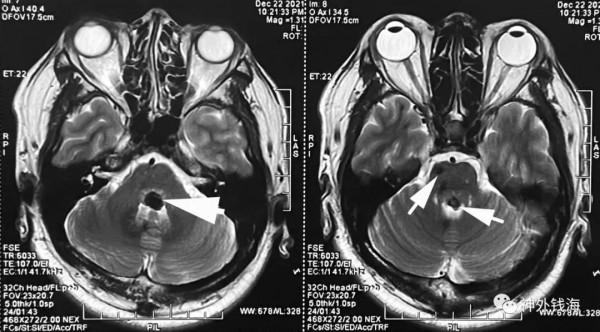

一例中年男性患者,因為視物模糊、左側眼瞼下垂,頭暈及左耳鳴前來就診,經術前檢查診斷為腦幹多發海綿狀血管瘤,一個在右側腦橋前方,另一個在腦橋背側中線位置。術前,我們考慮難以一次同時解決2處病變,故先處理腦橋背側的較大的一個病灶。患者的磁共振如圖:

圖1 磁共振T2序列可見2處海綿狀血管瘤病灶(白箭)。本次手術僅處理背側靠近中線的一處病灶。